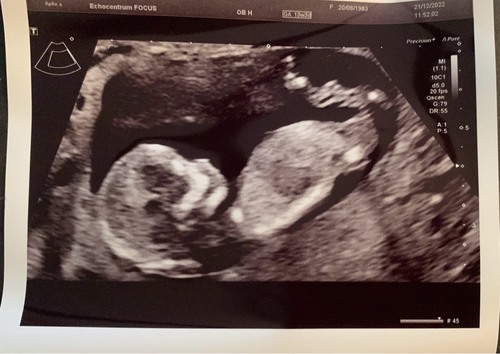

Vandaag de 13 weken echo gehad van onze tweeling. Alles was goed en ze lagen er als fotomodelletjes bij dat we binnen een half uur weer buiten stonden 😅. Zo verliefd en blij ❤️ (bovenste foto is kindje 1 aan het drinken)